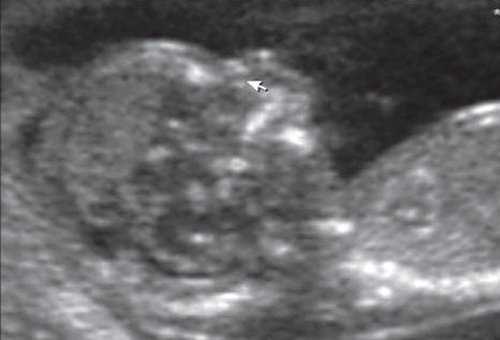

При эхографии в срок 13 недель 3 дня фетометрические параметры плода соответствовали гестационной норме, толщина воротникового пространства составила 1,5 мм; длина костей носа - по 2,5 мм. При трансвагинальном сканировании были обнаружены: затылочное энцефалоцеле размерами 7,4х3,5х3,7 мм (рис. 1), полидактилия кистей (рис. 2), увеличенные кистозно-измененные почки: правая - 28,5х21,3 мм; левая - 26,4х18,7 мм (рис. 3). Объем амниотической полости был нормальным для данного срока.

(Слева) ТАУЗИ плода в I триместре. Определяется умеренное утолщение воротникового пространства (кали-перы). По поводу неровных контуров задней части свода черепа выполнено ТВУЗИ.

(Справа) ТВУЗИ подтверждает наличие дефекта задней части свода черепа, а также затылочного энцефалоцеле крупных размеров, содержащее мозжечок целиком. Показан тщательный поиск других пороков развития.